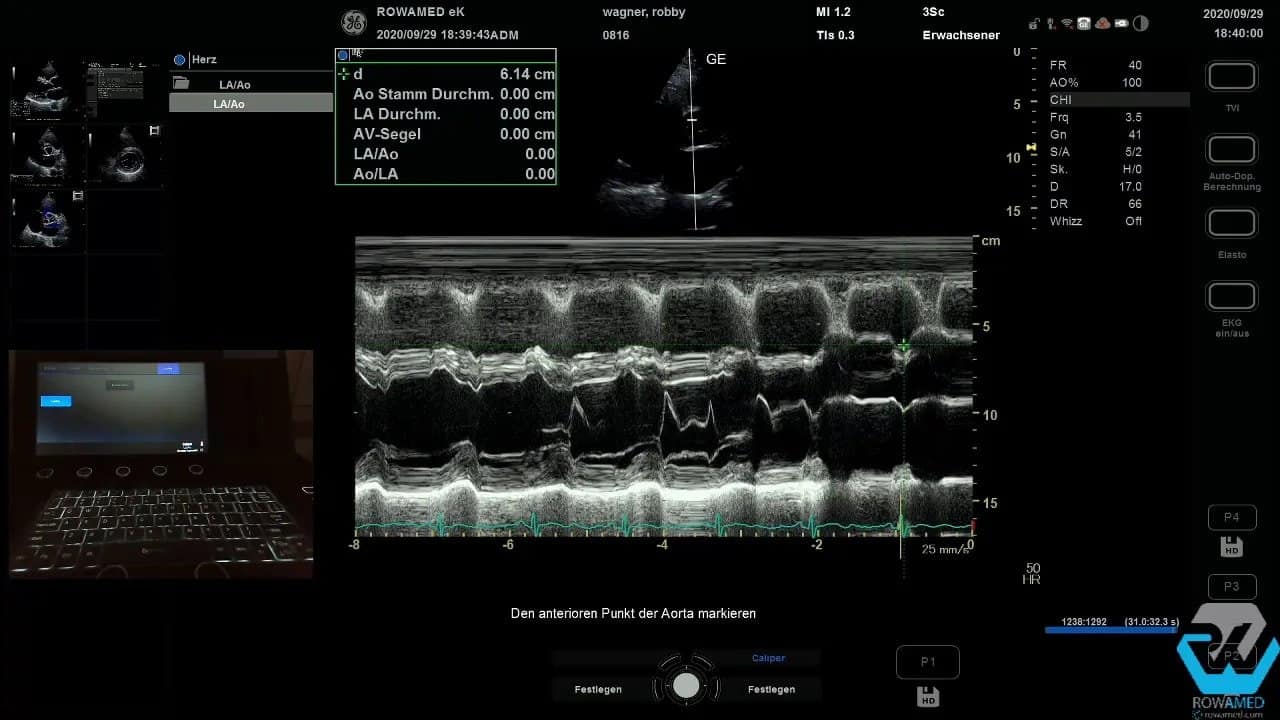

Step 6: Den M-Mode sinnvoll einsetzen

Der M-Mode wird manchmal als altmodisch abgetan. Das ist ein Fehler. In der Transthorakale Echokardiographie liefert er weiterhin sehr anschauliche, zeitlich hochaufgelöste Informationen. Wenn Sie den M-Mode-Strahl senkrecht durch den linken Ventrikel legen und anschließend einen Sweep von mittventrikulär Richtung Herzbasis durchführen, erhalten Sie mehrere Strukturen in einem Bild.

Typische Messgrößen sind:

- Aortenwurzel

- linker Vorhof

- Aortenklappen-Separation

- rechter Ventrikel

- Septumdicke

- linksventrikulärer Innendurchmesser

- posteriore Wanddicke

Der Charme des M-Mode liegt in seiner Übersicht. Mehrere lineare Messungen lassen sich in einem einzigen Datensatz dokumentieren. Für Lehre, Verlaufskontrolle und strukturierte Befundung ist das nach wie vor sehr hilfreich.